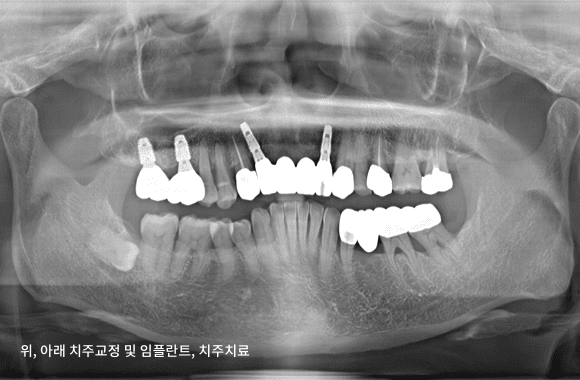

시니어 교정+임플란트